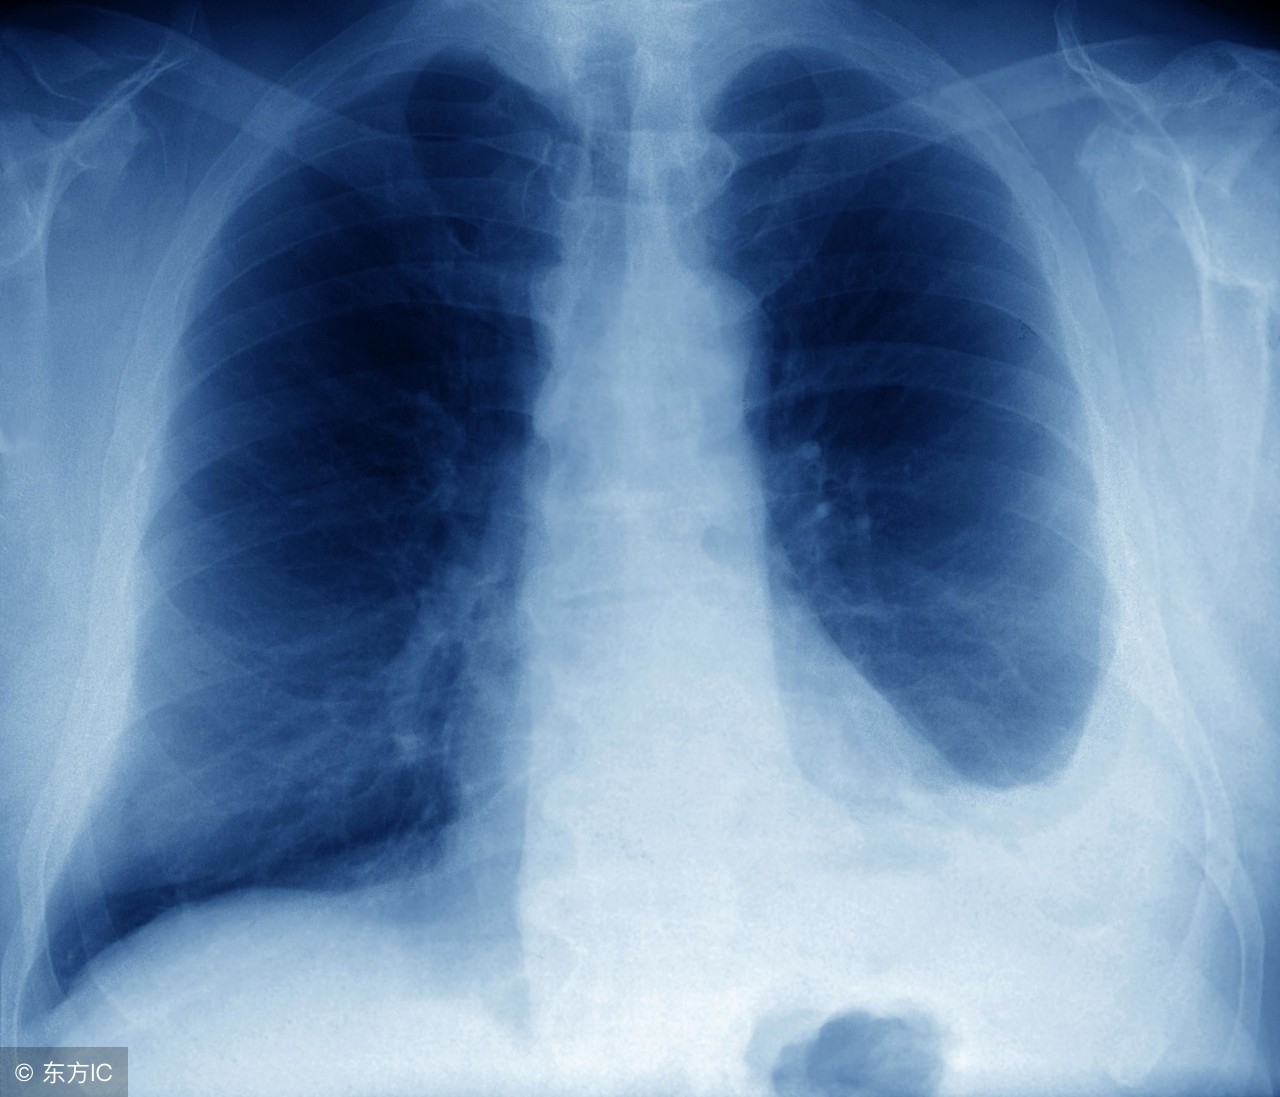

其它转移情势可能导致疼痛的方式都不一样。如果腹腔内广泛转移,多是腹部胀痛为主,肿瘤压迫肠管导致肠梗阻,会引起阵发性痉挛性疼痛;如果出现脑转移,会引起头晕、头胀痛,持续性,放疗可适当缓解;出现肺转移,轻度可没有症状,严重时会出现胸闷、胸痛等症状,化疗为主,胸水多时,适当放胸水,缓解症状。

左侧胸腔积液